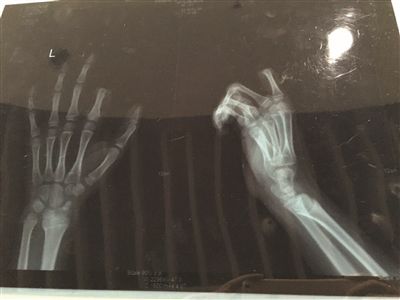

X光片显示孩子食指两个指节被切断。

不一会儿,饭做好了,听见这段对话的邹某,已经对小朋一直玩游戏的状态有些不满,便忍不住对小朋训斥了几句。当时,小朋手里正拿着叉子在叉土豆泥吃,听了爸爸训斥的话后,立马就炸毛了,放下手中的叉子,转身就拿起了身后矮桌上的菜刀,朝着自己的左手切下去,当场,食指的两个指节就掉了下来。

手术历经3个多小时。若能顺利度过一个星期的危险期,接上去的手指便能成活。苏州大学附属瑞华医院手外科主任周荣是小朋的主刀医生。下午1点不到,小朋便被推进手术室做准备,下午4点左右,小朋才被推出了手术室,转入病房。不幸中的万幸,经过三个多小时的手术,小朋的手指被暂时接上。

周荣说:“孩子年纪太小,血管也非常细,所以手术难度比较大,现在,手指已经被接上了,接下来便看他的恢复情况了?!本葜苋俳樯埽质鹾?,小朋的手一定不能乱动,否则很容易造成血管堵塞。如果小朋的配合程度高,顺利度过了一个星期的危险期,接上去的手指成活了,那么,这次事故对小朋今后生活的影响应该不大。